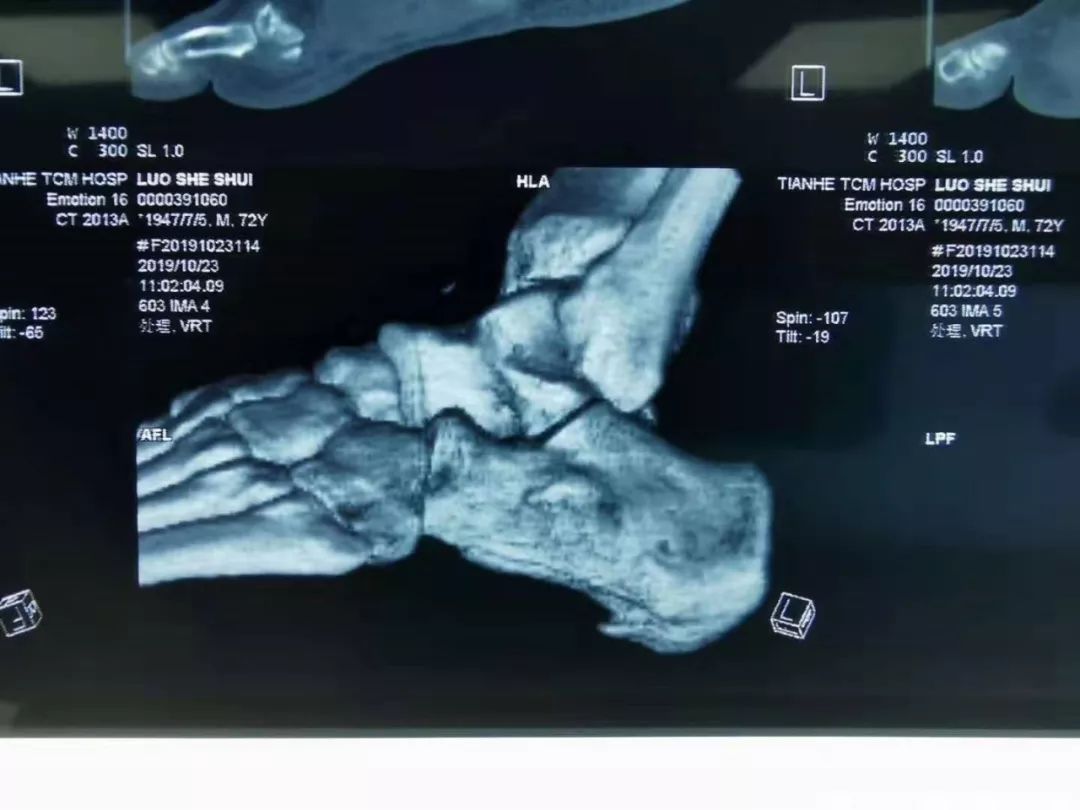

患者骆某 82岁,“反复左足跟疼痛走路困难4年”入院,经X线检查诊断为“左侧跟骨骨刺”。此前患者曾尝试各种治疗方法效果均不理想。

术前检查